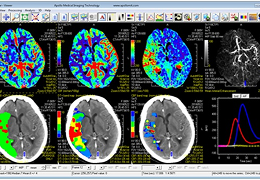

CTP Stroke Module produces high quality brain perfusion maps using fast and robust deconvolution algorithms coupled with Apollo's innovative noise reduction and motion artifact correction technologies.

CTP Stroke features both model processing and parametric curve analysis, easy identification of the arterial input function (AIF) from pixels of different slices, spatial and temporal noise reduction, and intelligent ROI and histogram analysis with automated region growing. Features include:

Cerebral Blood Volume

Cerebral Blood Flow

Mean Transit Time

Delay Time

Lesion map and volumes*

DT band map and volumes*

CBF band map and volumes*

mCTA and 4D DSA

Data courtesy of Prof. Mark Parsons, Melbourne Brain Centre, Royal Melbourne Hospital.